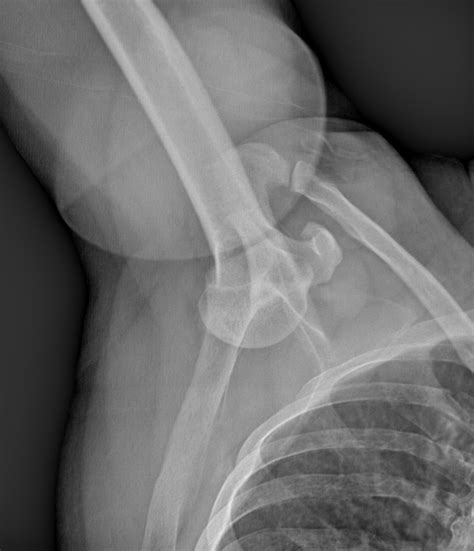

Diagnosis of Inferior Shoulder Dislocation

Diagnosing an inferior shoulder dislocation involves a combination of physical examination and imaging tests. The diagnostic process typically includes:

• Physical examination: A healthcare provider will assess the shoulder for deformity, swelling, and range of motion.

• X-rays: Imaging tests can confirm the dislocation and rule out fractures or other injuries.

• CT scan or MRI: These advanced imaging techniques may be used to evaluate the extent of the injury and plan treatment.

Accurate diagnosis is crucial for determining the appropriate course of treatment and ensuring a successful recovery.